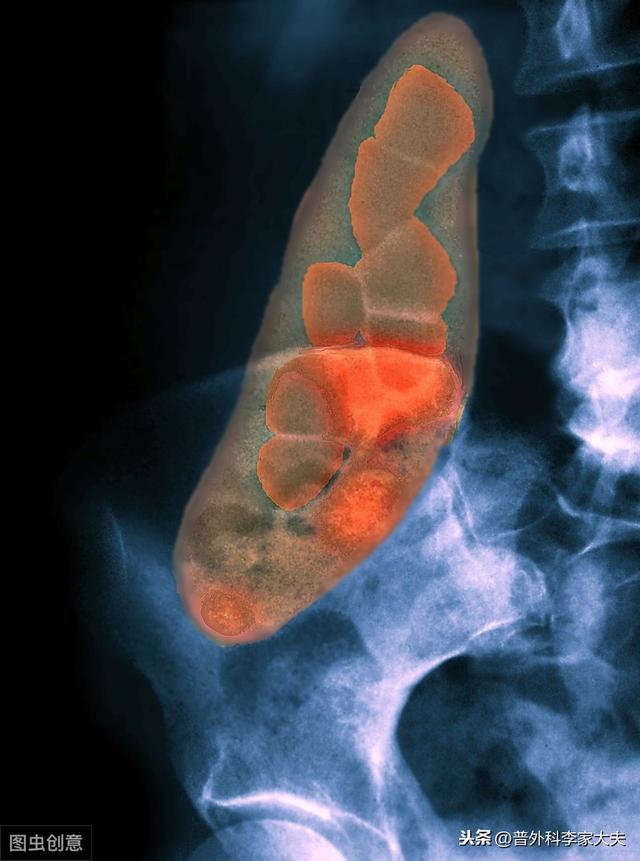

La cause clinique la plus fréquente de la cholécystite est le calcul biliaire. Avec l'amélioration du niveau de vie et la popularité de l'examen physique, l'incidence du calcul biliaire a tendance à augmenter. La proportion de personnes chez qui des calculs de la vésicule biliaire ont été détectés lors de l'examen physique a tendance à augmenter, ce qui correspond à la population asymptomatique souffrant de calculs de la vésicule biliaire. D'un point de vue clinique, les patients atteints de cholécystite sont plus nombreux à présenter des calculs de la vésicule biliaire.

La vésicule biliaire est située dans la partie supérieure droite de l'abdomen, à la base du foie, et constitue un élément important du système biliaire de l'organisme. Le symptôme typique de la cholécystite est une douleur dans la partie supérieure droite de l'abdomen, dont la nature est le plus souvent colique, et chez certains patients la douleur est si sévère et intolérable que nous l'appelons colique biliaire. La plupart d'entre eux ont pour facteur déclenchant la consommation d'aliments gras, l'examen de la douleur à la pression dans la partie supérieure droite de l'abdomen, le signe de Murphy est positif. L'échographie abdominale permet le plus souvent de voir une hypertrophie évidente de la vésicule biliaire, et la plupart d'entre eux peuvent trouver des calculs de la vésicule biliaire en même temps.

Le principe de la cholécystite pierreuse est que les calculs de la vésicule biliaire bloquent le canal de la vésicule biliaire, ce qui entraîne une stagnation de la bile, une croissance bactérienne et donc une infection. Le traitement est donc principalement une thérapie antibactérienne, les bactéries pathogènes communes étant principalement Escherichia coli et les bactéries anaérobies, le traitement antibactérien clinique céphalosporine + nitroimidazole. Comme il s'agit de bactéries purulentes, les infections graves peuvent provoquer une cholécystite septique, voire une perforation de la vésicule biliaire ; pour les calculs de la vésicule biliaire et la cholécystite, les cliniciens préfèrent généralement la cholécystectomie par laparoscopie.

Les calculs de la vésicule biliaire sont l'une des causes les plus probables de cholécystite aiguë, généralement en raison de l'obstruction soudaine des calculs biliaires ou de la douleur intense qui survient lorsque les calculs s'incrustent dans le canal de la vésicule biliaire. Les parasites et leurs métabolites peuvent également présenter des symptômes d'obstruction lors d'épidémies parasitaires antérieures, de même que la torsion du canal de la vésicule biliaire, les tumeurs et les infections bactériennes, qui sont également l'une des causes les plus courantes de cholécystite.

Les calculs de la vésicule biliaire étant un facteur pathogène majeur de la cholécystite, leur composition est considérée comme plus fréquente sur la base de l'analyse de la composition des cristaux de cholestérol.